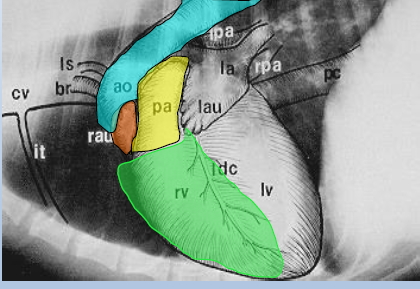

Ascending aorta

Right auricle

Pulmonary artery

Right ventricle

Cardiac silhouette

Left atrium

Left auricle

Left Ventricle